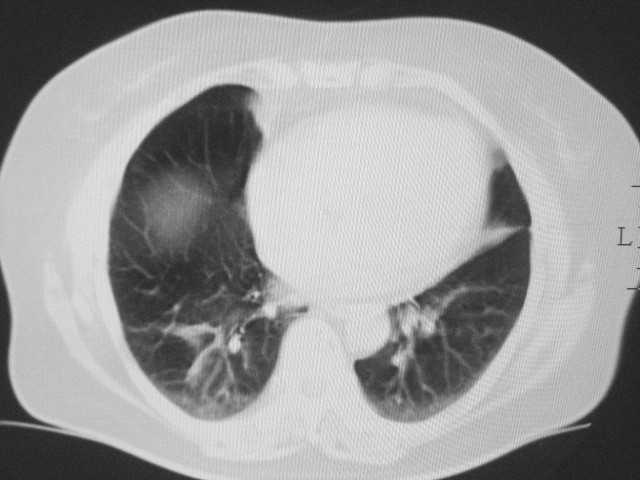

以下是引用清清楚楚在2007-8-28 7:13:00的发言:[br]右肺下叶可见斑片状高密度影,边缘模糊;右肺中叶内侧段及左肺舌段亦可见小斑片状模糊影。[br]考虑双肺感染,建议抗炎治疗后复查。

以下是引用天南地北在2007-8-27 23:49:00的发言:[br]右肺下叶可见斑片状高密度影,边缘模糊;右肺中叶内侧段及左肺舌段亦可见小斑片状模糊影。[br]考虑双肺感染,建议积极抗炎治疗后复查。

以下是引用天南地北在2007-8-27 23:49:00的发言:[br]右肺下叶可见斑片状高密度影,边缘模糊;右肺中叶内侧段及左肺舌段亦可见小斑片状模糊影。[br]考虑双肺感染,建议抗炎治疗后复查。

以下是引用难听在2007-8-28 13:17:00的发言:[br]右肺下叶背段支气管狭窄,是否可以考虑新生物伴阻塞性肺炎.请大家帮帮忙,这个病人是卫生局长的丈母娘.惹不起啊.